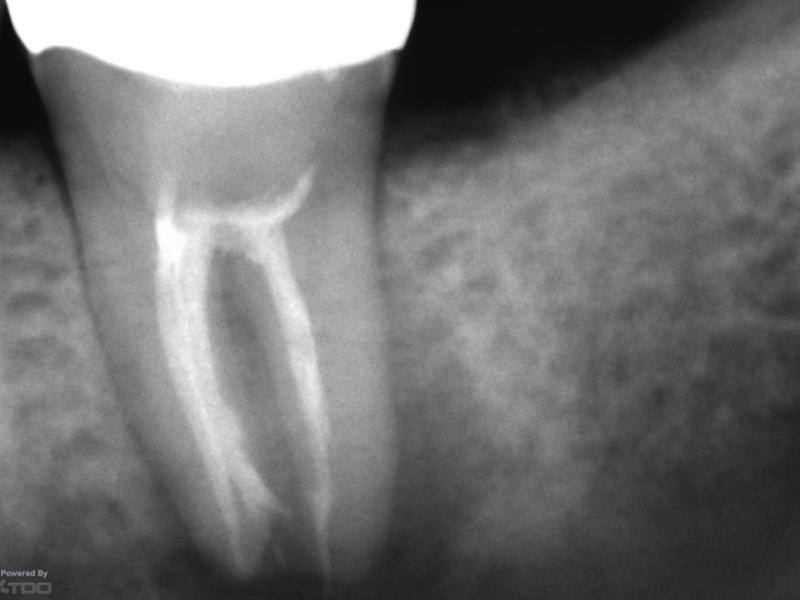

Recall